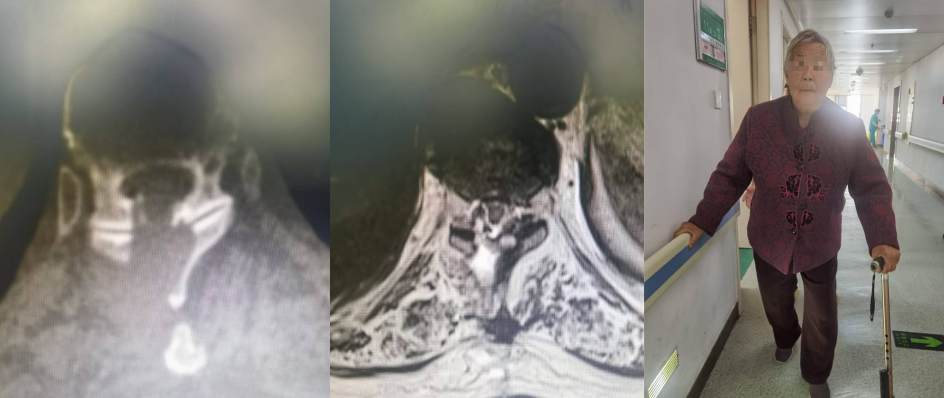

患者術(shù)后復(fù)查CT及MRI均顯示脊髓無明顯受壓,腦脊液通暢,術(shù)后患者下肢肌力級感覺明顯恢復(fù),已能下地行走